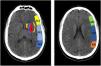

To determine the extension of the stroke and therefor consider different treatment options, we use the Alberta Stroke Program Early CT Score (ASPECTS) (Fig. 1).

Alberta Stroke Programme Early CT Score (ASPECTS). It is used for the interpretation of a CT or MRI scan (diffusion sequence) in ischaemic stroke involving the anterior circulation. Two axial planes are analysed, the first one at the level of the thalamus and basal ganglia (plane A), and the second at the corona radiata level, in which the basal ganglia are not visible (plane B). The territory of the middle cerebral artery (MCA) in these 2 planes has been divided into 10 regions, each of which is assessed at 1 point. These regions are: L: lentiform nucleus (putamen); C: caudate; IC: internal capsule; I: insular ribbon; M1: Anterior MCA cortex; M2: MCA cortex lateral to insular ribbon; M3: posterior MCA cortex; M4, M5, M6: anterior, lateral and posterior territory of the MCA, approximately 2 cm superior to M1, M2 and M3, respectively. Based on this analysis, one point is deducted from the initial 10 for each region exhibiting early signs of ischaemia (hypodensity or local mass effect). Scores of 7 points or less are associated with poor functional recovery and high morbidity and mortality, with a higher risk of intraparenchymal haemorrhage. A score of 10 corresponds to a normal CT scan.